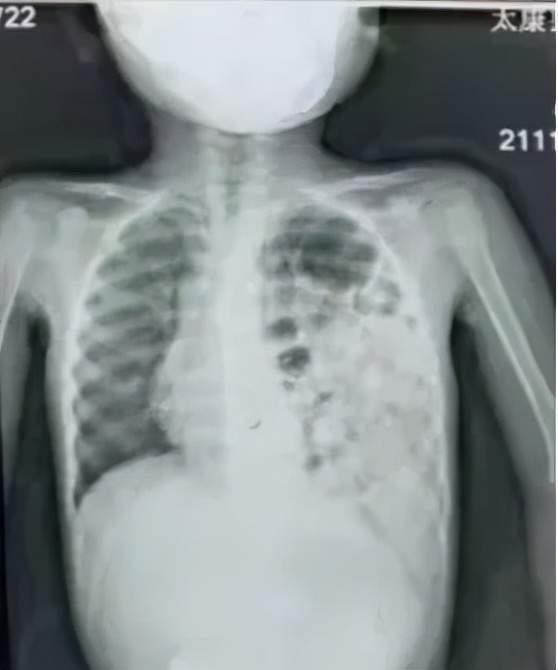

术后在胸腔镜视野下,可看到楠楠的左侧胸腔内充满了胃和肠子,而左肺则受压变小,医生们帮助腹腔各脏器回到它们原本的位置,紧接着修补了缺损的膈肌,最后让受压的左肺重新膨开了。

胸腔镜手术的顺利完成大大减少了对患儿创伤,为预后打下了良好的基础。